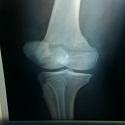

Lésion exceptionnelle : genou flottant bilatéral

Younes Ouchrif, Issam Elouakili

PAMJ. 2014; 19: 28. Published 12 September 2014